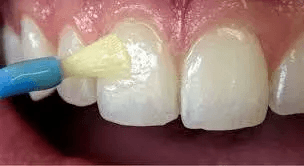

A sticky, honey-like material applied to the teeth with a small brush

Strengthens tooth enamel & helps prevent tooth decay

Most effective when applied several times per year